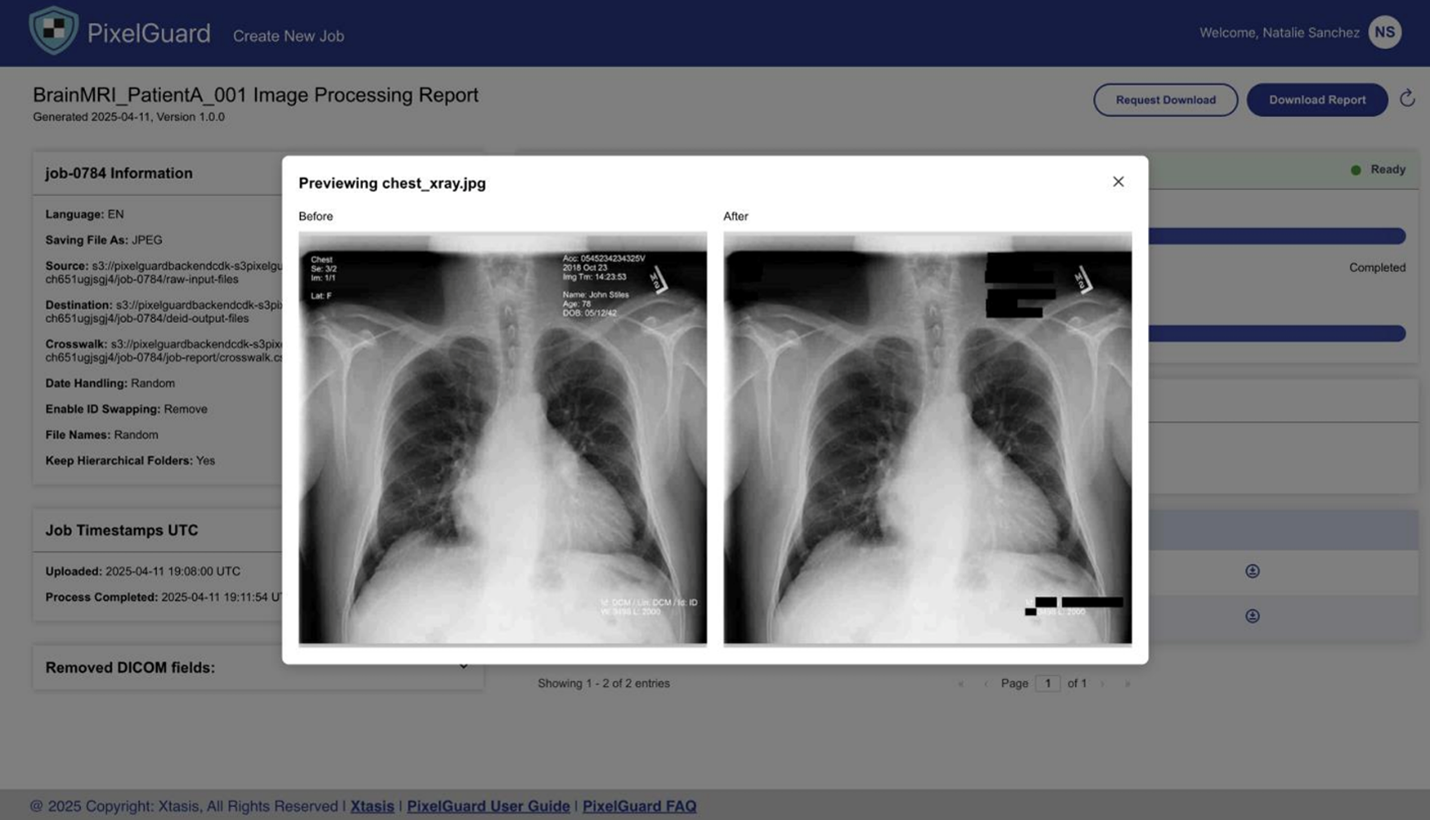

PixelGuard—built on Amazon Web Services (AWS) and created by Northwestern University Assistant Professor and Founder of Xtasis, LLC, Dr. Adrienne Kline—is an advanced software solution that deidentifies medical images while preserving clinical relevance and efficacy. It uses over 75 state-of-the-art AI-driven models capable of detecting and redacting multilingual, multi-orientation text across all major formats (DICOM, JPEG, PNG, NIfTI, etc.), alongside configurable metadata anonymization. With an intuitive UI, enterprise SSO, and in-tenant deployment (no data egress), PixelGuard delivers secure, compliant, and high-throughput image de-identification. PixelGuard is available on AWS Marketplace. ScaleCapacity—an AWS Partner—was instrumental in the development of the UI, cloud infrastructure, and deployment to AWS Marketplace.

The de-identification of medical images necessitates metadata and pixel data scrubbing. In some situations, the metadata may need to be anonymized rather than removed entirely. When the metadata is anonymized rather than removed, the anonymization process must not in any way dilute the research value of the image. For example, a medical image of a 20-year-old cannot be anonymized to indicate that the image belongs to an 80-year-old, because that may dilute the research value.

To scrub pixel data, optical character recognition (OCR) to detect burned-in text can be used. This must be used in conjunction with machine learning (ML) models to locate and blur areas with identifying information. ML models can also be used to generate a confidence score associated to the blurring of information. For images where the confidence score is below a certain pre-defined threshold, a human review queue can also be defined for investigation and possible approval.

The following images provide an overview of the image redaction experience using PixelGuard.